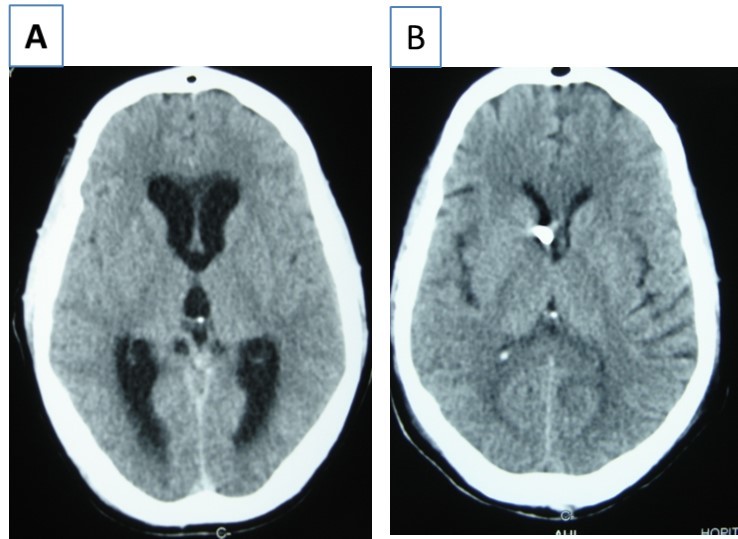

Patient was placed on intra veinous amphotéricin B but this was complicated with acute active hydrocephalus warranting external ventricular drainage (Figure 3). Subsequently, he developped staphylococcal meningitis as day 8 post op, treated with intra veinous vancomycin. Patient developed renal insufficiency and hyperosmolar non ketotic coma for an unknown diabetis for which amphotéricine B therapy was stopped. His neurological status deteriorated with a Glasgow coma scale (GCS)7/15. Posterior fossa surgery was performed with excision of the fungal abscess (Figure 4) and Voriconazol was instituded post operatively for fungal therapy with improvement of the neurological status to GCS 13/15. But the patient succumbed to acute cardiac failure.

Figure 3.cerebral CT scan with axial view showing acute hydrocephalus (A) and control after external ventricular drainage (B)